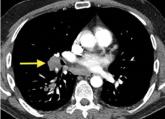

A young man presents with severe, pressure-like, midsternal, nonradiating pain, rated 10 on a scale of 10.